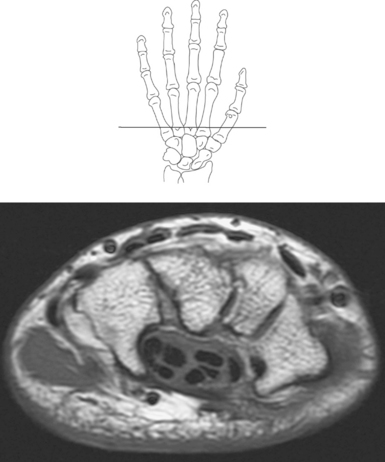

The bony anatomy of the wrist and hand consists of the distal radius and ulna, 8 carpal bones, 5 metacarpals, and 14 phalanges (Figure 9.101). Both the distal radius and ulna have a conical styloid process that acts as an attachment site for ligaments. The radial styloid process is located on the lateral surface of the radius, whereas the ulnar styloid process is located on the posteromedial side of the ulna. The carpal bones are arranged in proximal and distal rows. Located in the proximal row of carpal bones are the scaphoid (navicular), lunate (semilunar), triquetral (triquetrum), and pisiform bones. The pisiform is considered a sesamoid bone that is embedded in the tendon of the flexor carpi ulnaris. The distal row consists of the trapezium (greater multangular), trapezoid (lesser multangular), capitate (os magnum), and hamate (unciform) bones (Figures 9.102 through 9.114). The five metacarpals are small tubular bones with a proximal end (base), distal end (head), and shaft (body). The 14 phalanges that make up the fingers are short tubular bones. Like the metacarpals, each phalanx consists of a proximal (base), middle (body or diaphysis), and distal (head) portion. Each digit consists of 3 phalanges (proximal, middle, and distal), except for the thumb (first digit), which has only 2 phalanges (proximal and distal). The articulation of the phalanges of the second through fifth digits creates three interphalangeal joints: the metacarpophalangeal (MCP) joints classified as condyloid joints, proximal interphalangeal (PIP), and distal interphalangeal (DIP). The proximal and distal interphalangeal joints are classified as hinge joints (Figure 9.101). The first digit, which consists of 2 phalanges, has just two joints: the MCP joint, classified as a saddle joint, and an interphalangeal joint, classified as a hinge joint (Figure 9.101).

Numerous ligaments provide additional stability to the wrist. The extrinsic ligaments reinforce the joint cavity surrounding the carpal region and include palmar and dorsal radial carpal ligaments, the radial and ulnar collateral ligaments, and the TFCC (Figures 9.115 through 9.117). The many articulations between the carpal bones are supported by the intercarpal ligaments or intrinsic ligaments that connect the carpal bones to each other (Figure 9.115). The configuration of the intrinsic ligaments, metacarpal ligaments, and triangular fibrocartilage complex creates five different joint compartments that can be demonstrated at arthrography: (1) compartment of the first carpometacarpal articulation, (2) common carpometacarpal compartment, (3) mediocarpal compartment, (4) intermetacarpal compartment, and (5) radiocarpal compartment (Figure 9.115). The carpal tunnel is created by the concave arrangement of the carpal bones (Figure 9.103). A thick ligamentous band called the flexor retinaculum (transverse carpal ligament) stretches across the carpal tunnel to create an enclosure for the passage of tendons and the median nerve (Figures 9.118 through 9.120). The flexor retinaculum inserts medially on the pisiform and hook of the hamate and spans the wrist to insert laterally on the scaphoid and trapezium. In addition to the carpal tunnel, another tunnel called Guyon’s canal is formed where the ulnar extension of the flexor retinaculum continues over the pisiform and hamate. This creates a potential site for compression of the ulnar nerve (Figures 9.118, top, and 9.119). The extensor retinaculum (dorsal carpal ligament), located dorsally, is much thinner. It attaches medially to the ulnar styloid process, triquetrum, and pisiform and laterally to the lateral margin of the radius (Figure 9.120, left). Along its course it forms six fibroosseous tunnels for the passage of the synovial sheaths containing the extensor tendons (Figure 9.118, bottom).